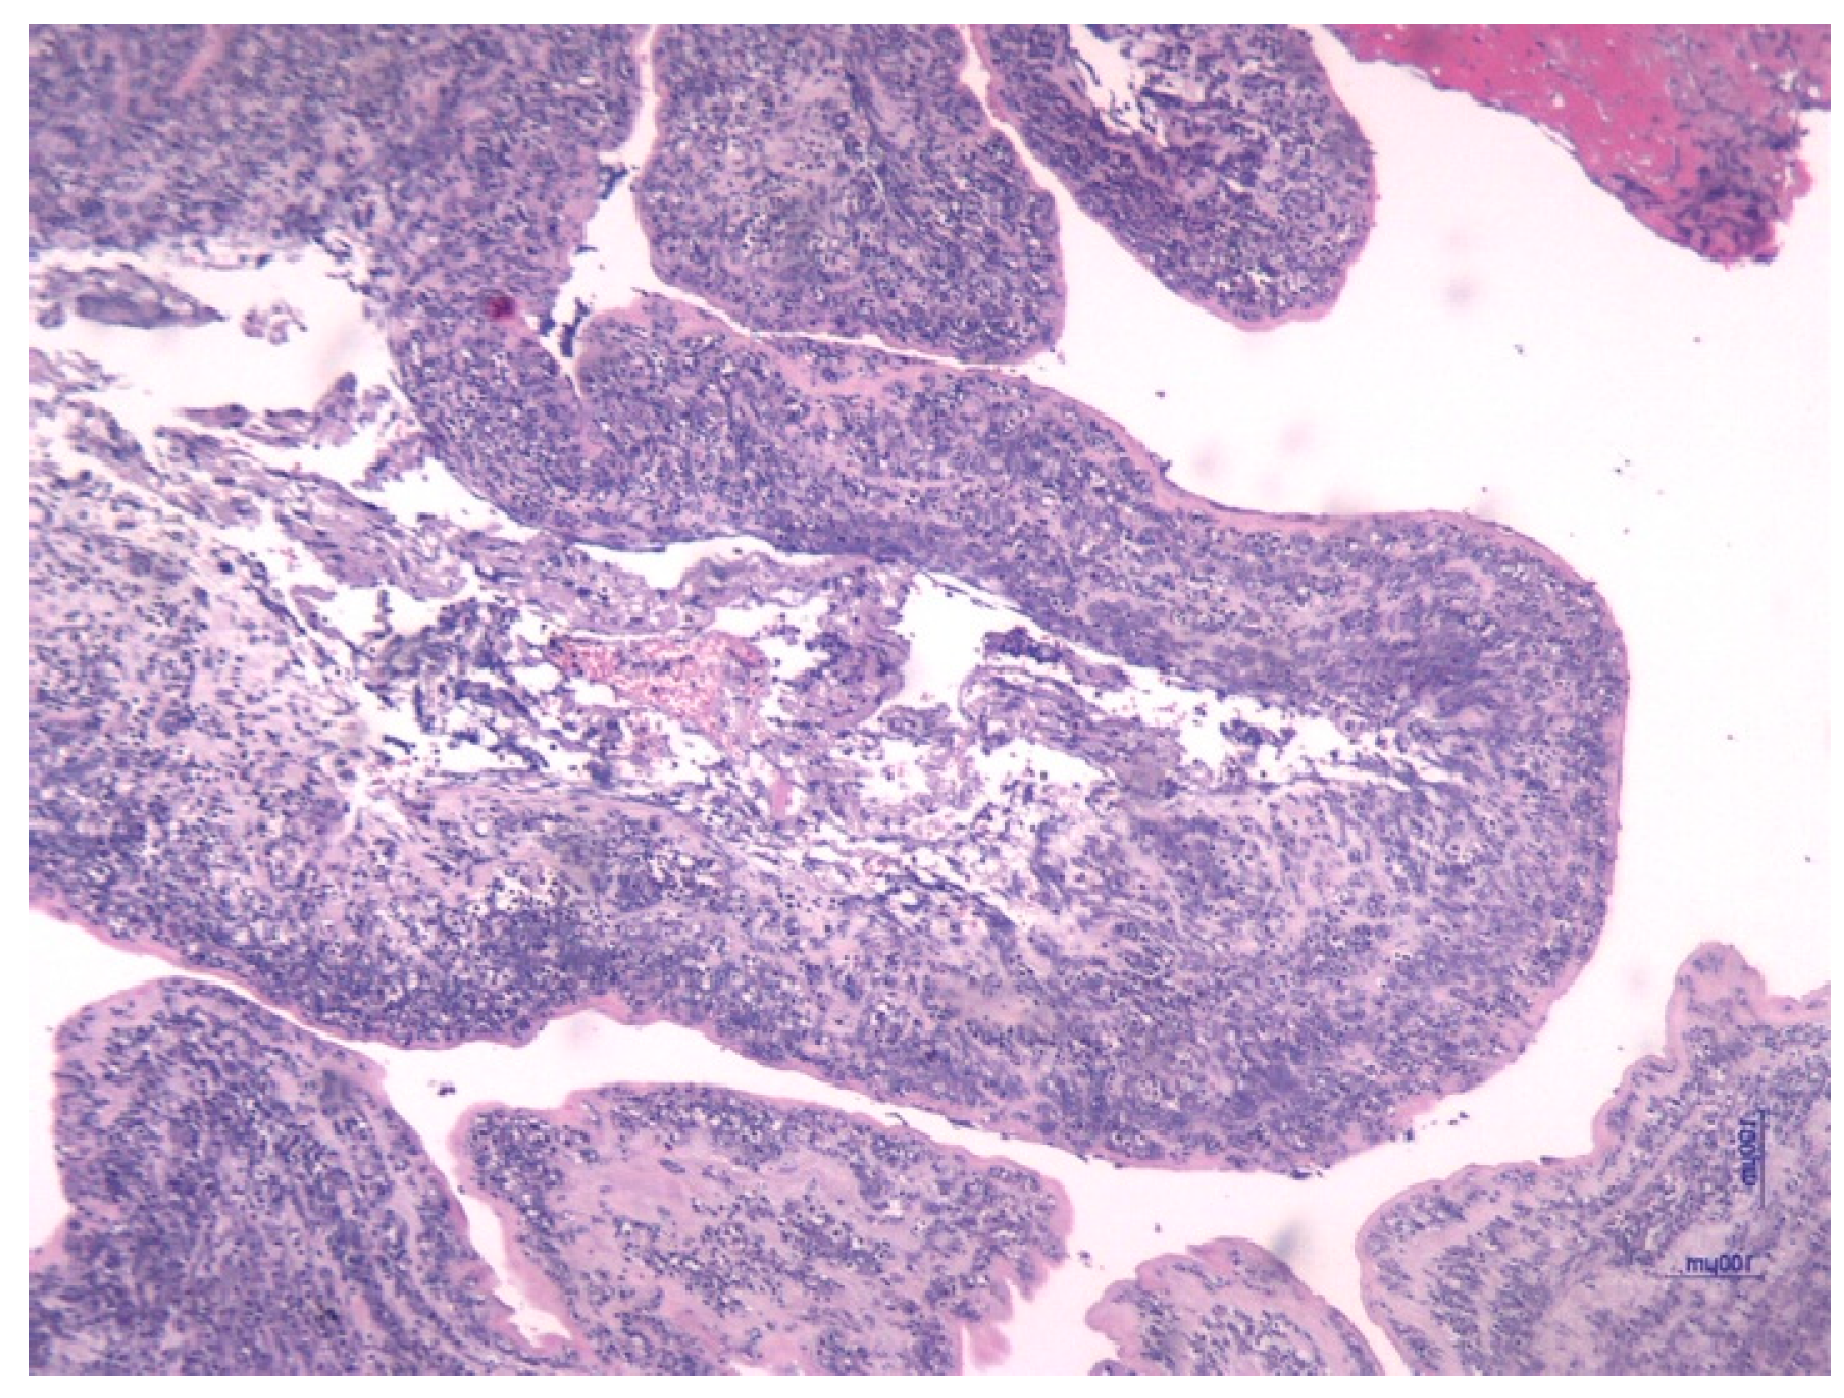

- Pacora, P.; Chaiworapongsa, T.; Maymon, E.; Kim, Y.M.; Gomez, R.; Yoon, B.H.; Ghezzi, F.; Berry, S.M.; Qureshi, F.; Jacques, S.M.; et al. Funisitis and chorionic vasculitis: The histological counterpart of the fetal inflammatory response syndrome. J. Matern. Neonatal Med. 2002, 11, 18–25. [Google Scholar] [CrossRef]

- Kim, C.J.; Romero, R.; Chaemsaithong, P.; Chaiyasit, N.; Yoon, B.H.; Kim, Y.M. Acute chorioamnionitis and funisitis: Definition, pathologic features, and clinical significance. Am. J. Obstet. Gynecol. 2015, 213 (Suppl. 4), S29–S52. [Google Scholar] [CrossRef] [PubMed]

| Corioamnionitis (n = 42) | 37 (88.1%) | 5 (11.9%) | 0.001 | |

| Funisitis (n = 37) | 33 (89.2%) | 4 (10.8%) | 0.001 | |